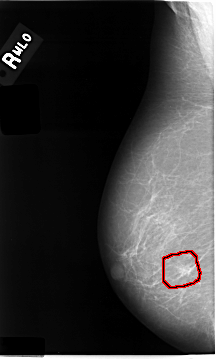

ics_version 1.0 filename C-0014-1 DATE_OF_STUDY 22 6 1992 PATIENT_AGE 83 FILM FILM_TYPE REGULAR DENSITY 1 DATE_DIGITIZED 11 9 1997 DIGITIZER LUMISYS LASER SEQUENCE LEFT_CC LINES 4648 PIXELS_PER_LINE 2696 BITS_PER_PIXEL 12 RESOLUTION 50 NON_OVERLAY LEFT_MLO LINES 4632 PIXELS_PER_LINE 2824 BITS_PER_PIXEL 12 RESOLUTION 50 NON_OVERLAY RIGHT_CC LINES 4608 PIXELS_PER_LINE 2624 BITS_PER_PIXEL 12 RESOLUTION 50 OVERLAY RIGHT_MLO LINES 4664 PIXELS_PER_LINE 2800 BITS_PER_PIXEL 12 RESOLUTION 50 OVERLAY |

FILE: C_0014_1.RIGHT_MLO.OVERLAY TOTAL_ABNORMALITIES 1 ABNORMALITY 1 LESION_TYPE MASS SHAPE IRREGULAR MARGINS MICROLOBULATED ASSESSMENT 5 SUBTLETY 4 PATHOLOGY MALIGNANT TOTAL_OUTLINES 1 BOUNDARY |